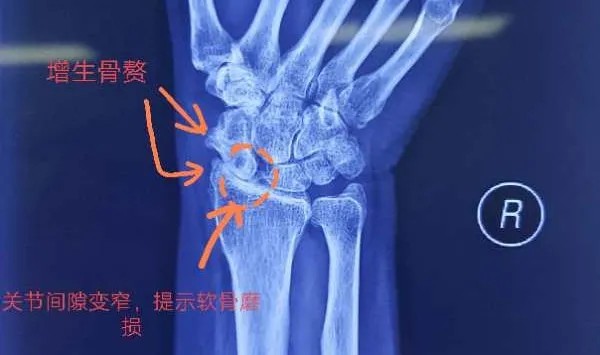

患者马某是一位来自农村的普通家庭妇女,被右腕关节疼痛长期困扰,辗转就诊于焦作及周边多家大型医院,病情并未好转。经过多方打听最终就诊于我院,经过详细的问诊、查体及影像学检查,最终确诊为“右腕关节炎伴舟骨坏死”,这种疾病在临床上非常常见,但是由于传统手术技术的限制,治疗效果并不理想